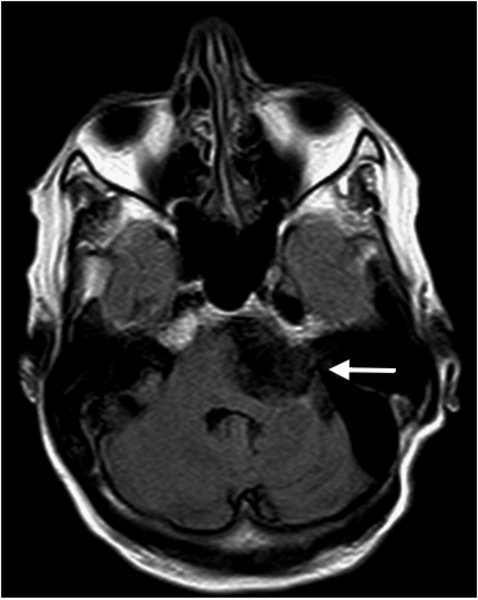

Epidermoid - T2 - axial

Liquorintenses Signal in T2

DD: Arachnoidalzyste, mit  Liquorsignal in allen Sequenzen